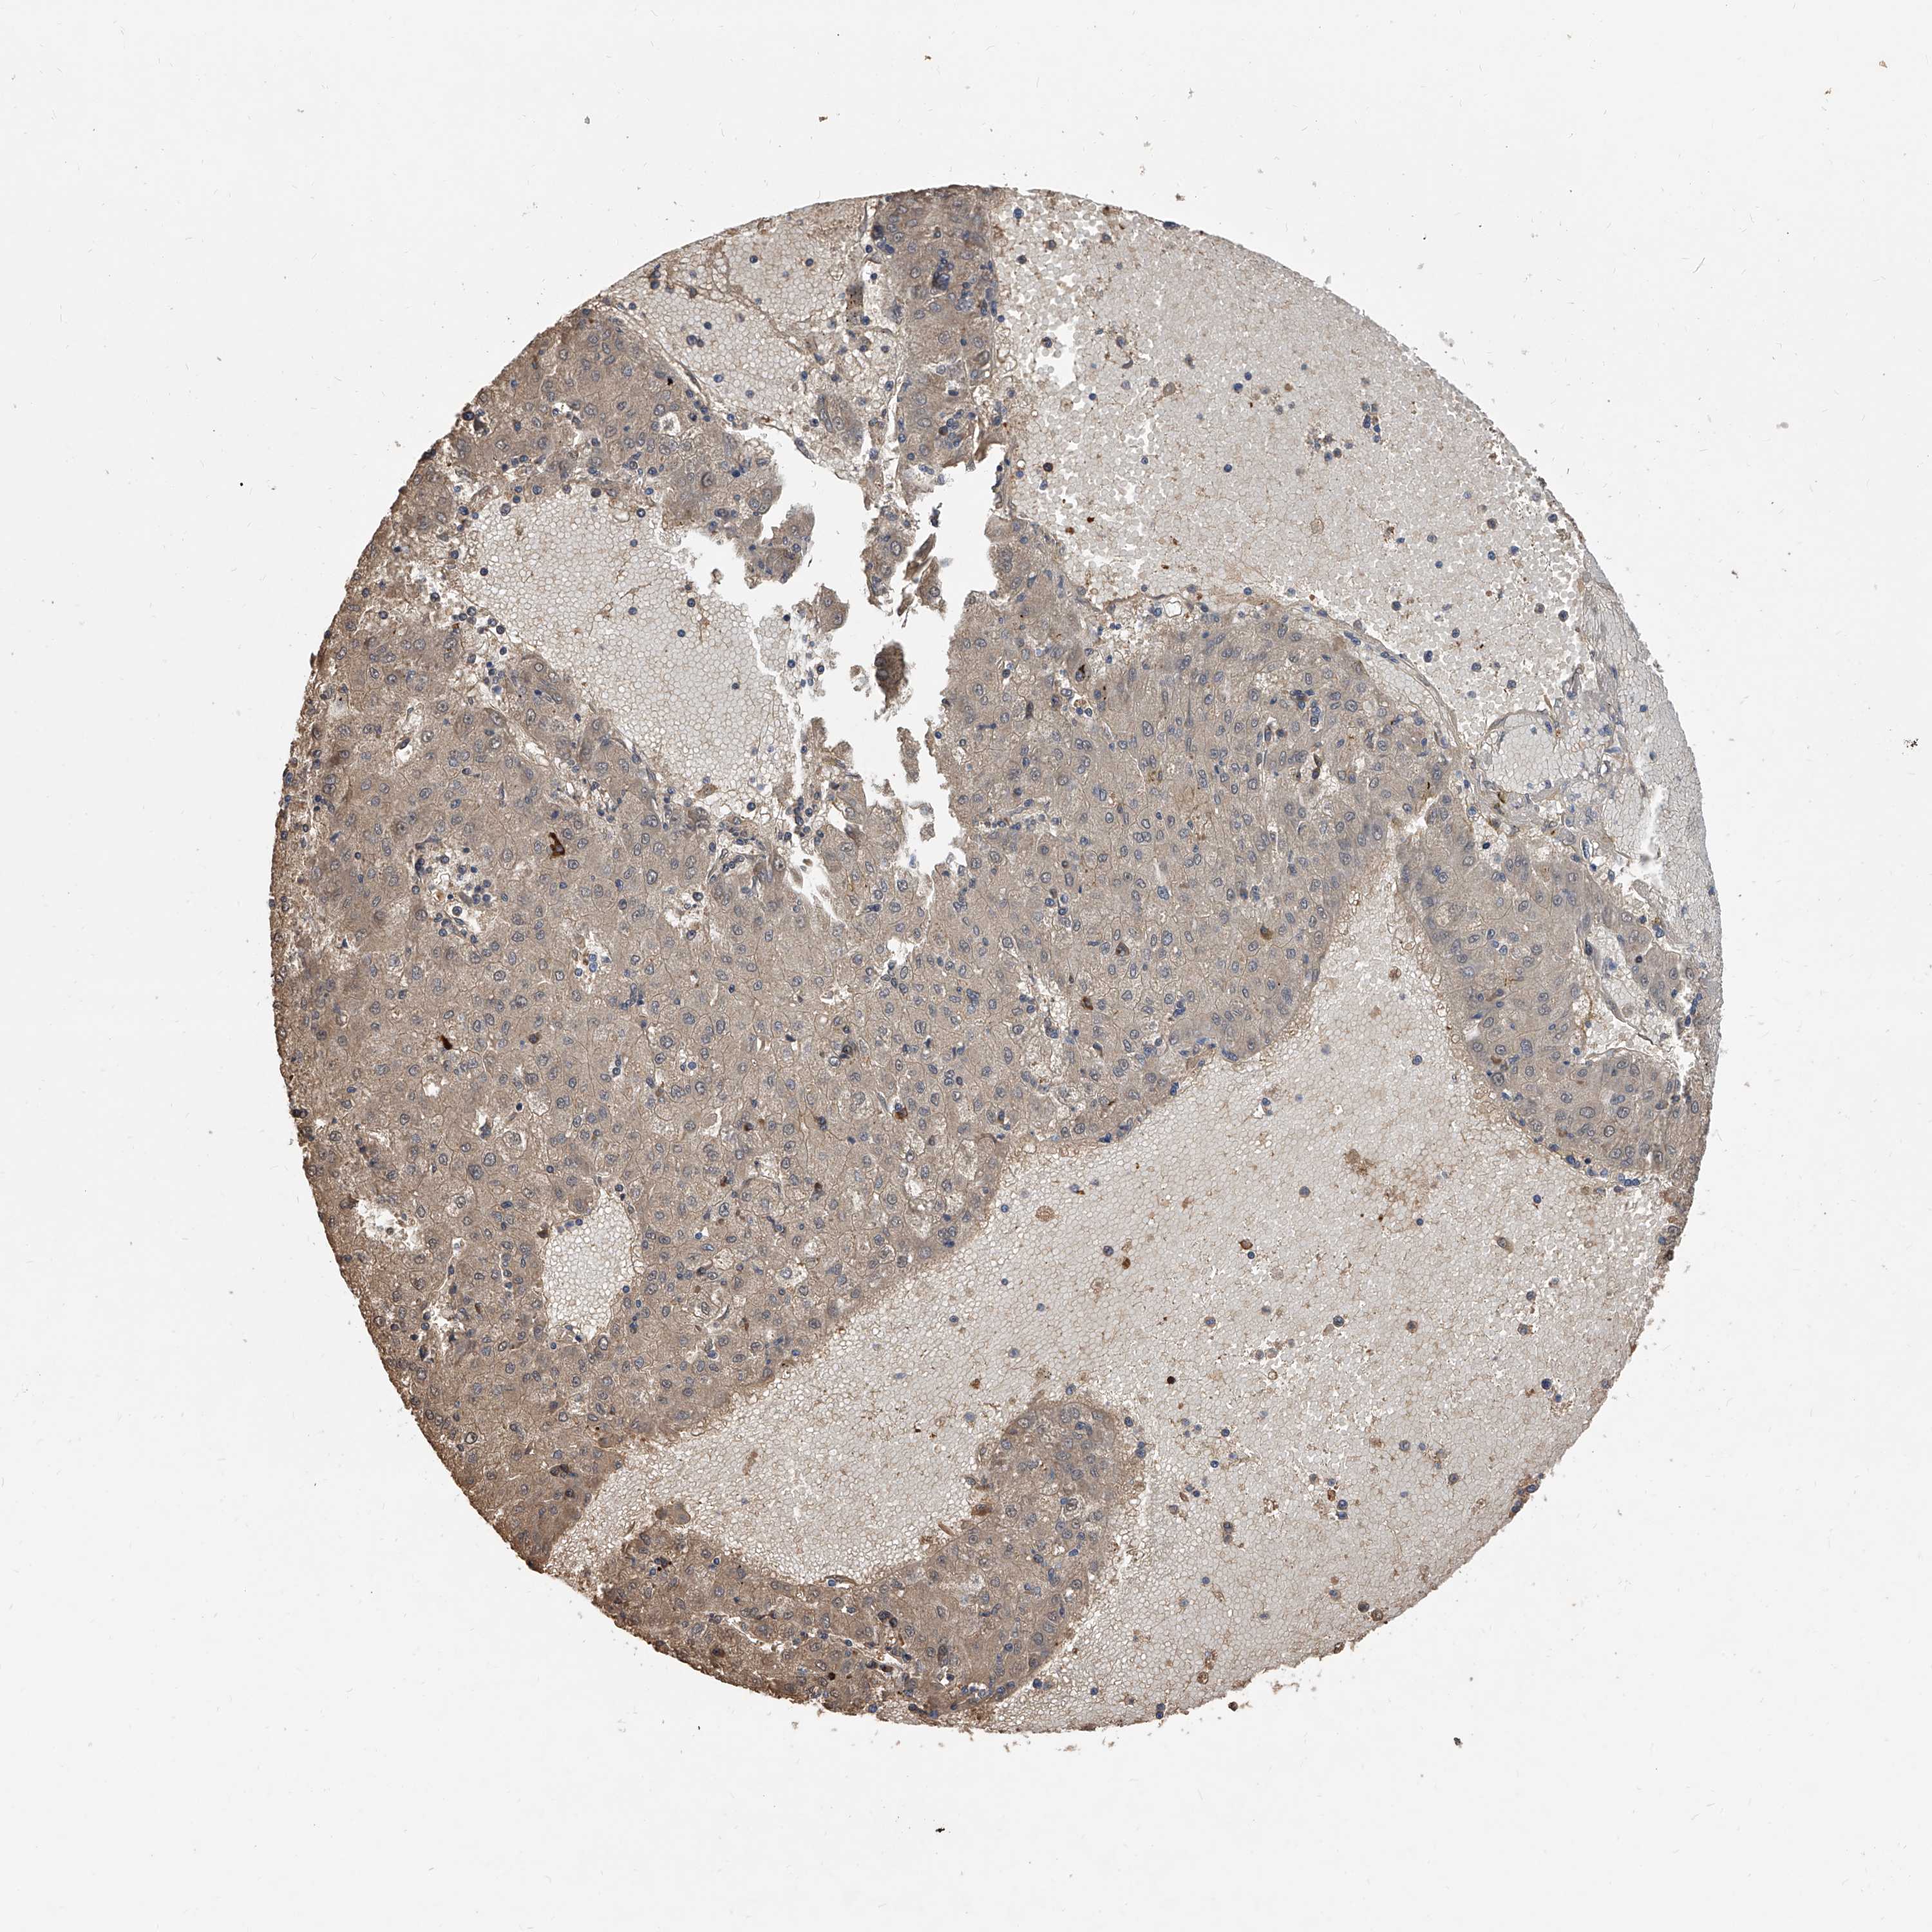

LIVER CANCER - Protein expressioni

A mouse-over function shows sample information and annotation data. Click on an image to view it in a full screen mode. Samples can be filtered based on level of antibody staining by selecting one or several of the following categories: high, medium, low and not detected. The assay and annotation is described here.

Note that samples used for immunohistochemistry by the Human Protein Atlas do not correspond to samples in the TCGA dataset.

Antibody stainingi

Antibody staining in the annotated cell types in the current human tissue is reported as not detected, low, medium, or high, based on conventional immunohistochemistry profiling in selected tissues. This score is based on the combination of the staining intensity and fraction of stained cells.

Each image is clickable and will lead to virtual microscopy that enables deeper exploration of all samples and also displays staining intensity scores, fraction scores and subcellular localization as well as patient and tissue information for each sample.

Antibody HPA030190

Staining

High

Medium

Low

Not detected

Intensity

Strong

Moderate

Weak

Negative

Quantity

>75%

75%-25%

<25%

None

Location

Nuclear

Cytoplasmic/membranous

Cytoplasmic/membranous,nuclear

Cholangiocarcinoma

Carcinoma, Hepatocellular, NOS